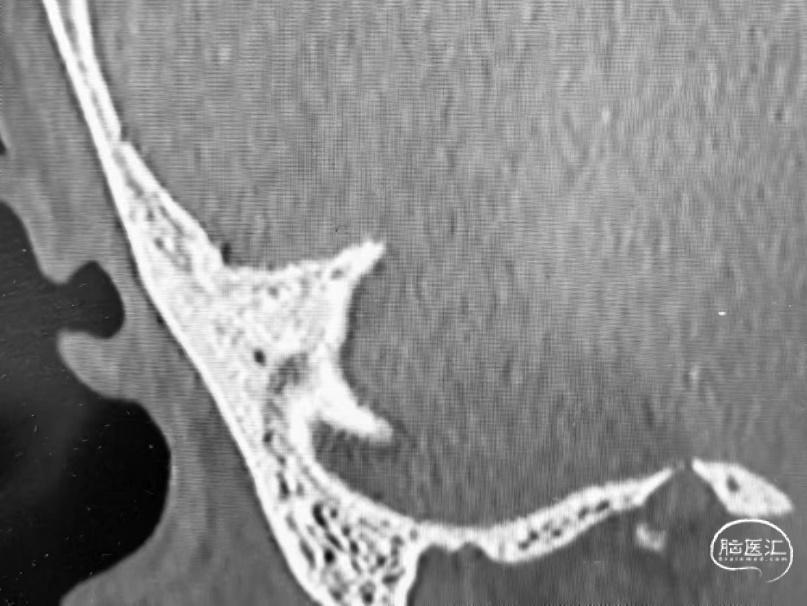

➤CT

高位颈内静脉

支架到位难度高